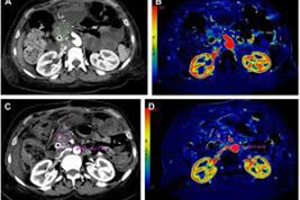

Since 1993, Star Test Diagnosis and Imaging Center has been put into service with the aim of reaching higher quality service, more satisfied